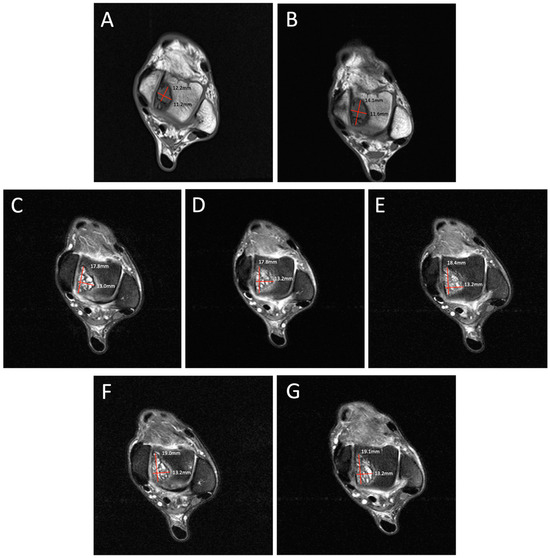

Figure 1.

Degenerative progression of the left medial osteochondral lesion outlined in red on axial MRIs from 2009 to 2021. The timeline of lesion progression includes MRI scans from 2009 (

A), 2011 (

B), 2016 (

C), 2017 (

D), 2018 (

E), 2019 (

F), and 2021 (

G). This axial view demonstrates the osteoarthritic progression of the lesion from 12.2 mm × 11.2 mm in 2009 to 19.1 mm × 13.2 mm in 2021. Patient Case Report: A 72-year-old male presented to the outpatient foot and ankle clinic with a 16-year history of bilateral ankle pain. The patient’s symptoms first began in 2007 following an exercise-induced injury that was left untreated. The patient described his pain as an intermittent waxing and waning sensation of dull pain and aches. Physical examination demonstrated tenderness localized to the anterior aspect of both ankles. Ankle movements were free and without pain. Stability testing revealed mild increased laxity with anterior drawer and talar tilt. He had no other significant past medical history that would contribute to his orthopedic condition. Following his injury, the patient underwent bilateral ankle magnetic resonance imaging (MRI) beginning in 2009, which revealed osteochondral lesions of the talus (OLTs) in both ankles. The patient continued to receive serial ankle MRIs over the following years to monitor the course of the osteochondral lesions over time, totaling seven MRI scans between 2009 and 2021 (